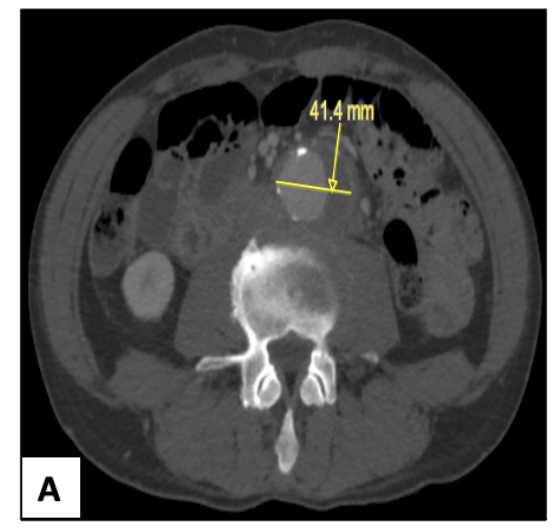

A 61-year-old man with a history of cerebral stroke, hypertension, dyslipidemia, appendectomy, sinusitis, hiatal hernia, smoking, and alcohol abuse was admitted to the internal medicine department for investigation of a digestive disorder. Anamnesis revealed chronic intermittent abdominal pain associated with diarrhea and nausea. A loss of 12 kg over 6 months was reported. At his first admission, physical examination identified a thin, febrile patient (temperature: 39° C [102° F;] body mass index, 18.3 kg/m2) with a normal heart rate. The abdomen was slightly tender and painful at palpation without any other anomalies. Samples of blood, stool, and urine were obtained for culture. All of the cultures were negative except for the blood culture that grew C. fetus. Additional laboratory tests showed hemoglobin count, 14.2 g/dL; platelets, 242 G/L; leukocytes, 8 G/L; creatinine clearance, 98 mL/min; potassium, 3.9 mmol/L; calcium, 2.6 mg/dL; and albumin, 41.6 g/L. C-reactive protein (CRP) and natremia were abnormal at 174 mg/L and 127 mmol/L, respectively. A positron emission tomography scan showed esophagitis with an intense fixation at the stomach, and a fixation at the left colic angle as well. Fibroscopy and a thoraco-abdomino-pelvic computed tomography (CT) scan revealed no particularities. However, an infrarenal AAA was seen, measuring 42 mm x 33 mm (Figure 1).

Total colposcopy with resection of 3 polyps at the left colon showed tubular adenoma with low-grade dysplasia. Bronchoscopy with bronchoalveolar lavage as well as serology of human immunodeficiency virus, hepatitis B and C, Lyme disease, Epstein-Barr virus, prostate-specific antigen, and lactate dehydrogenase were negative. The patient was diagnosed with C. fetus colitis and was given IV amoxicillin clavulanate (1 g 3 times/day for 10 days). One month later, he was readmitted for recurrence of the same symptoms. This time, testing showed a patent biologic inflammatory syndrome (anemia, 9.4 g/dL; thrombocytosis, 1038 G/L; and CRP, 229 mg/L). An abdomino-pelvic CT scan identified left pyelocaliceal dilation without a detected obstacle and an empyema measured at 35 mm plus abscessed collections measuring at most 25 mm. The aortic aneurysm had increased in diameter, reaching 65 mm x 40 mm and 79 mm at its greatest axis (Figure 1). Ureterohydronephrosis of the left kidney was also identified. Findings on transthoracic echocardiogram were normal. A transesophageal echocardiogram ruled out endocarditis. Blood culture grew C. fetus, and urine and feces cultures were sterile. Ultimately, strong IV antibiotic therapy was immediately initiated based on a consult from infectious disease specialists (amoxicillin clavulanate 2 g/4 hours and gentamicin 180 mg/24 hours). Given the high risk of rupture, an urgent surgical repair of the AAA was considered, preceded by the placement of a double J stent to treat ureterohydronephrosis. Through a midline laparotomy, an excision of the mycotic aneurysm and establishment of vascular continuity using allograft bypass in the infrarenal aortic bilateral common iliac arteries were performed (Figure 2). Pre- and post-operative courses were uneventful except for a blood transfusion.